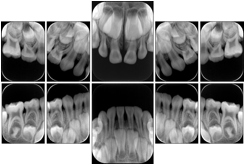

2. A patient requests cosmetic surgery to enhance their facial appearance. The case requires consultation between an orthodontist in New York and an oral surgeon in California. The cephalometric series of 2D projections constructed from the volumetric CT data that is used for the discussion is arranged by a Structured Display for transfer between the two practitioners.

Cephalometric Series Structured Display

Figure OO-2. Cephalometric Series Structured Display